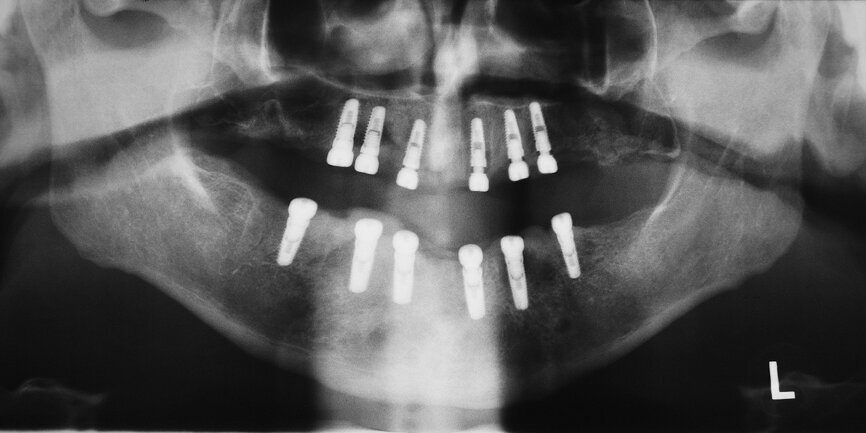

Deux petits lambeaux de pleine épaisseur ont également été décollés afin d’éliminer la vis d’ostéosynthèse utilisée pour stabiliser la greffe osseuse autologue de la chirurgie d’augmentation précédente (Fig. 9). L’insertion des implants a été réalisée à l’aide d’une clé à cliquet DRM et d’une douille standard, avec un couple de serrage prédéfini de 35–45 Ncm, afin de parvenir à une stabilité primaire maximale. Les façonneurs gingivaux ont été insérés avec un couple de serrage de 20 Ncm (Fig. 10) et, après l’insertion des implants, les lambeaux ont été suturés au moyen de fils non résorbables (Prolene 5/0). Les sutures ont été retirées après sept jours. Une tomographie panoramique dentaire postopératoire a permis de visualiser les implants insérés dans la mandibule. Les zones d’augmentation osseuse étaient également clairement reconnaissables sur les deux cotés (Fig. 11).

19 : Résultat de l’implantation avec tous les implants in situ.

Fig. 20 : Tomographie panoramique dentaire du patient aux fins du contrôle du résultat final.

L’insertion des implants a été réalisée à l’aide de la clé à cliquet DRM et de la douille standard, avec un couple de serrage d’environ 35–45 Ncm, afin de parvenir à une stabilité primaire maximale (Fig. 17). Par la suite, les tenons pour navigation implantaire et le guide chirurgical ont été retirés du maxillaire pour y insérer les façonneurs gingivaux, avec un couple de serrage de 25 Ncm (Figs. 18 et 19). Une technique similaire a été utilisée pour la préparation des lits implantaires et l’insertion des implants dans la mandibule, ou six implants CAMLOG de 4,3 mm in diamètre et de 11,0 mm de longueur ont été insérés sous guidage total dans les sites dentaires 15, 14, 12, 22, 24 et 25. Une tomographie panoramique dentaire postopératoire a permis de visualiser les implants insérés dans le maxillaire et la mandibule (Fig. 20).